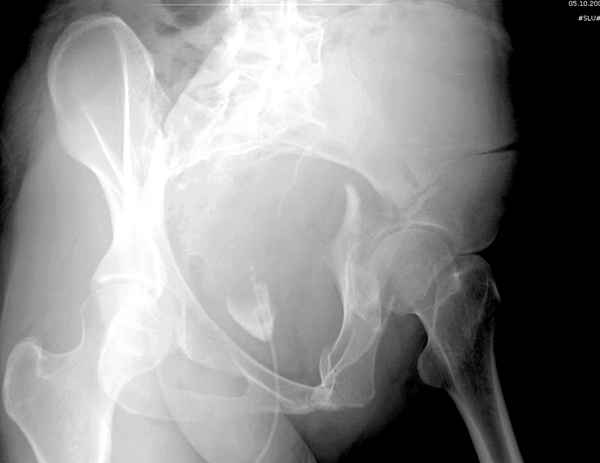

Интересно было бы посмотреть рентгенограммы до операции. У меня впечатление, что я не все вижу, что тут есть... Уважаемые Господа "тазисты" и "тазологи", к какому типу переломов вертлужной впадины по Летурнелю вы бы отнесли это случай?

Из переломов проходящих через крыло и/или заднюю стенку ни простой перелом "передней колонны" (явно имеется пером задней стенки, и не видно перелома седалищной или лонной), ни простой "поперечный", ни ассоциированный "Т-образный" (т.к есть перелом крыла и не видно перелома седалишной), ни ассоциированный "задняя колонна+задняя стенка", на ассоциированный "поперечный+задняя стенка", ни ассоциированный "передняя колонна+задняя гемисфера" (не видно перелома седалищной), ни ассоциированный "обе колонны" (не видно перелома лонной седалищной) не подходят под эту классификацию....

>Вопрос к знатокам: Так что это?

к таковым себя не причисляю, но...обычное дело для нашей страны - выкладывать 3D и не показывать стандартные проекции Judet. Дигност представляет те ракурсы, которые по-его мнению наиболее информативны, более того комп сам достраивает какие-то мелкие повреждения по 3D по своему усмотрению. По данной реконструкции можно предполагать высокий двухколонный перелом с оскольчатыми передней и задней колоннами, оскольчатую высокую переднюю колонну с задним полупоперечником или одно из перечисленных с вовлечение КПС. У меня впечатление за второй вариант, но нужно обследовать нормально - проекции, сканы.

мы имеем дело с полупоперечным переломом у которого отломался задний край или его отломали, превратив перелом в полный двухколонный.

По отдельным срезам и тем более по реконструкции трудно судить о сращении крыла и задней колонны с осевым скелетом.

Хорошо бы на рентгенограммы взглянуть и побольше срезов по своду. С каким отломком головка контактирует и как ее состояние.

Все выступающие коллеги высказались насчет необходимости стандартных снимков по Judet, потому что для определения тактики лечения переломов вертлужной впадины 3Д снимки малоинформативны.

Летурнель разработал классификсацию на основании прямого, запирательного и подвздошного рентген снимков, котоые, кроме описания характера переломов, также подсказывают адекватный доступ для репозиции перелома.